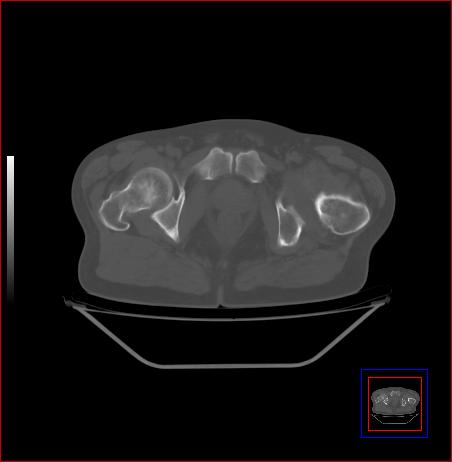

标题: CT15143:髋关节结核?

男,49,髋关节疼痛1年,无肺结核。

支持左侧髋关节结核合并轻度半脱位

骨质破坏,硬化,周围软组织脓肿,支持骨结核

骨质破坏,硬化,周围软组织脓肿,关节间隙增宽,支持骨结核